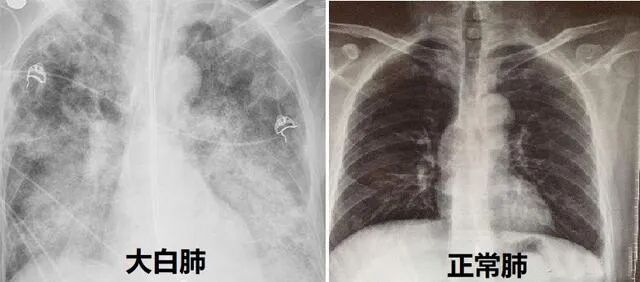

闺蜜她平时身体很好,这次却被奥密克戎击倒了。1月2日去闵行区中心医院看发热门诊,在医院里直接就不行了。血压66:44,大白肺,没了知觉,从来没有糖尿病的她血糖升至28,意识已经模糊,只感觉很远的地方传来医生的声音,跟她说不要担心,在医院里我们会全力救治,不会有生命危险,一定会给你治好。抢救她时,医生都是一路小跑,非常非常好的医生。当天就服用了辉瑞特效药加激素治疗,现在已经渐渐康复。